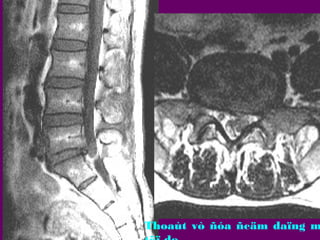

Thoaùt

vò

ñóa

ñeäm

Thoaùi hoaù-Thoaùt

vò ñóa ñeäm- Daøy

daây chaèng vaøng-

Thoaùt vò ñóa ñeäm

Thoaùt vò ñóa ñeäm daïng m